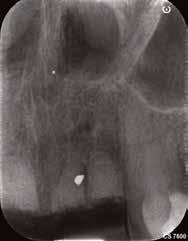

Miután a páciens egészségbiztosítója jóváhagyta a kezelési tervet, a négy frontfog eltávolításával megkezdtük a terápiát. Miután ez megtörtént, az alveolusokat EthOss degranulációs fúrók segítségével alaposan kitisztítottuk, majd EthOss csontpótlóval töltöttük ki a gyökerek helyeit, hogy segítsük a seb primer záródását és a gyógyulását (5. ábra).

Két hónappal a fogeltávolítást követően készült egy újabb CBCT a felső állcsontról (7. ábra), illetve ismét vettünk egy digitális lenyomatot a DEXIS IS 3800 intraorális szkenner segítségével (8. ábra) . Ezek a lépések nélkülözhetetlenek az implantátumok helyének megtervezéséhez, illetve a sebészi sablon elkészítéséhez. A 3D szoftveres tervezés során az implantátumok pozícióinak meghatározása elsősorban a protetikai szempontok szerint történt (9–10. ábra). A sebészi fúrósablont is ennek megfelelően, egy sebészi sablonok tervezésére alkalmas szoftverrel terveztük meg és készítettük el (11. a–c ábra) . Mind a négy hiányzó fog területét megvizsgáltuk, majd kiválasztottuk azokat a legoptimálisabb és legjobban hozzáférhető területeket, ahova két implantátum és egy hídpótlás kerülhet. A tervezési fázist követően egy sebészi fúrósablont készíttettünk Stratasys 3D nyomtatóval, MED610 rezinből (Stratasys). Ezt követően behelyezésre került két implantátum (4,1 x 12,0 mm, Straumann Bone Level, Tapered, Regular CrossFit, SLActive, Roxolid), a precizitást a Straumann Guided Surgery szettje biztosította. A 2.1es fog gyökércsúcsa feletti csontban található amalgámdarabot óvatosan eltávolítottuk, egy apró szemcse maradt csupán az ínyben (12. ábra) . Az implantátumok

megfelelő gyógyulása és integrációja érdekében a bukkális csontot ismét augmentáltuk EthOss csontpótlóval, majd zártuk a sebet úgynevezett félig zárt (semi-submerged) technikával (13. a–b ábra)